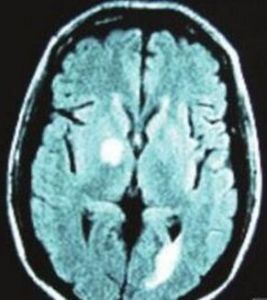

CTMRI檢查有助於鑑別診斷。